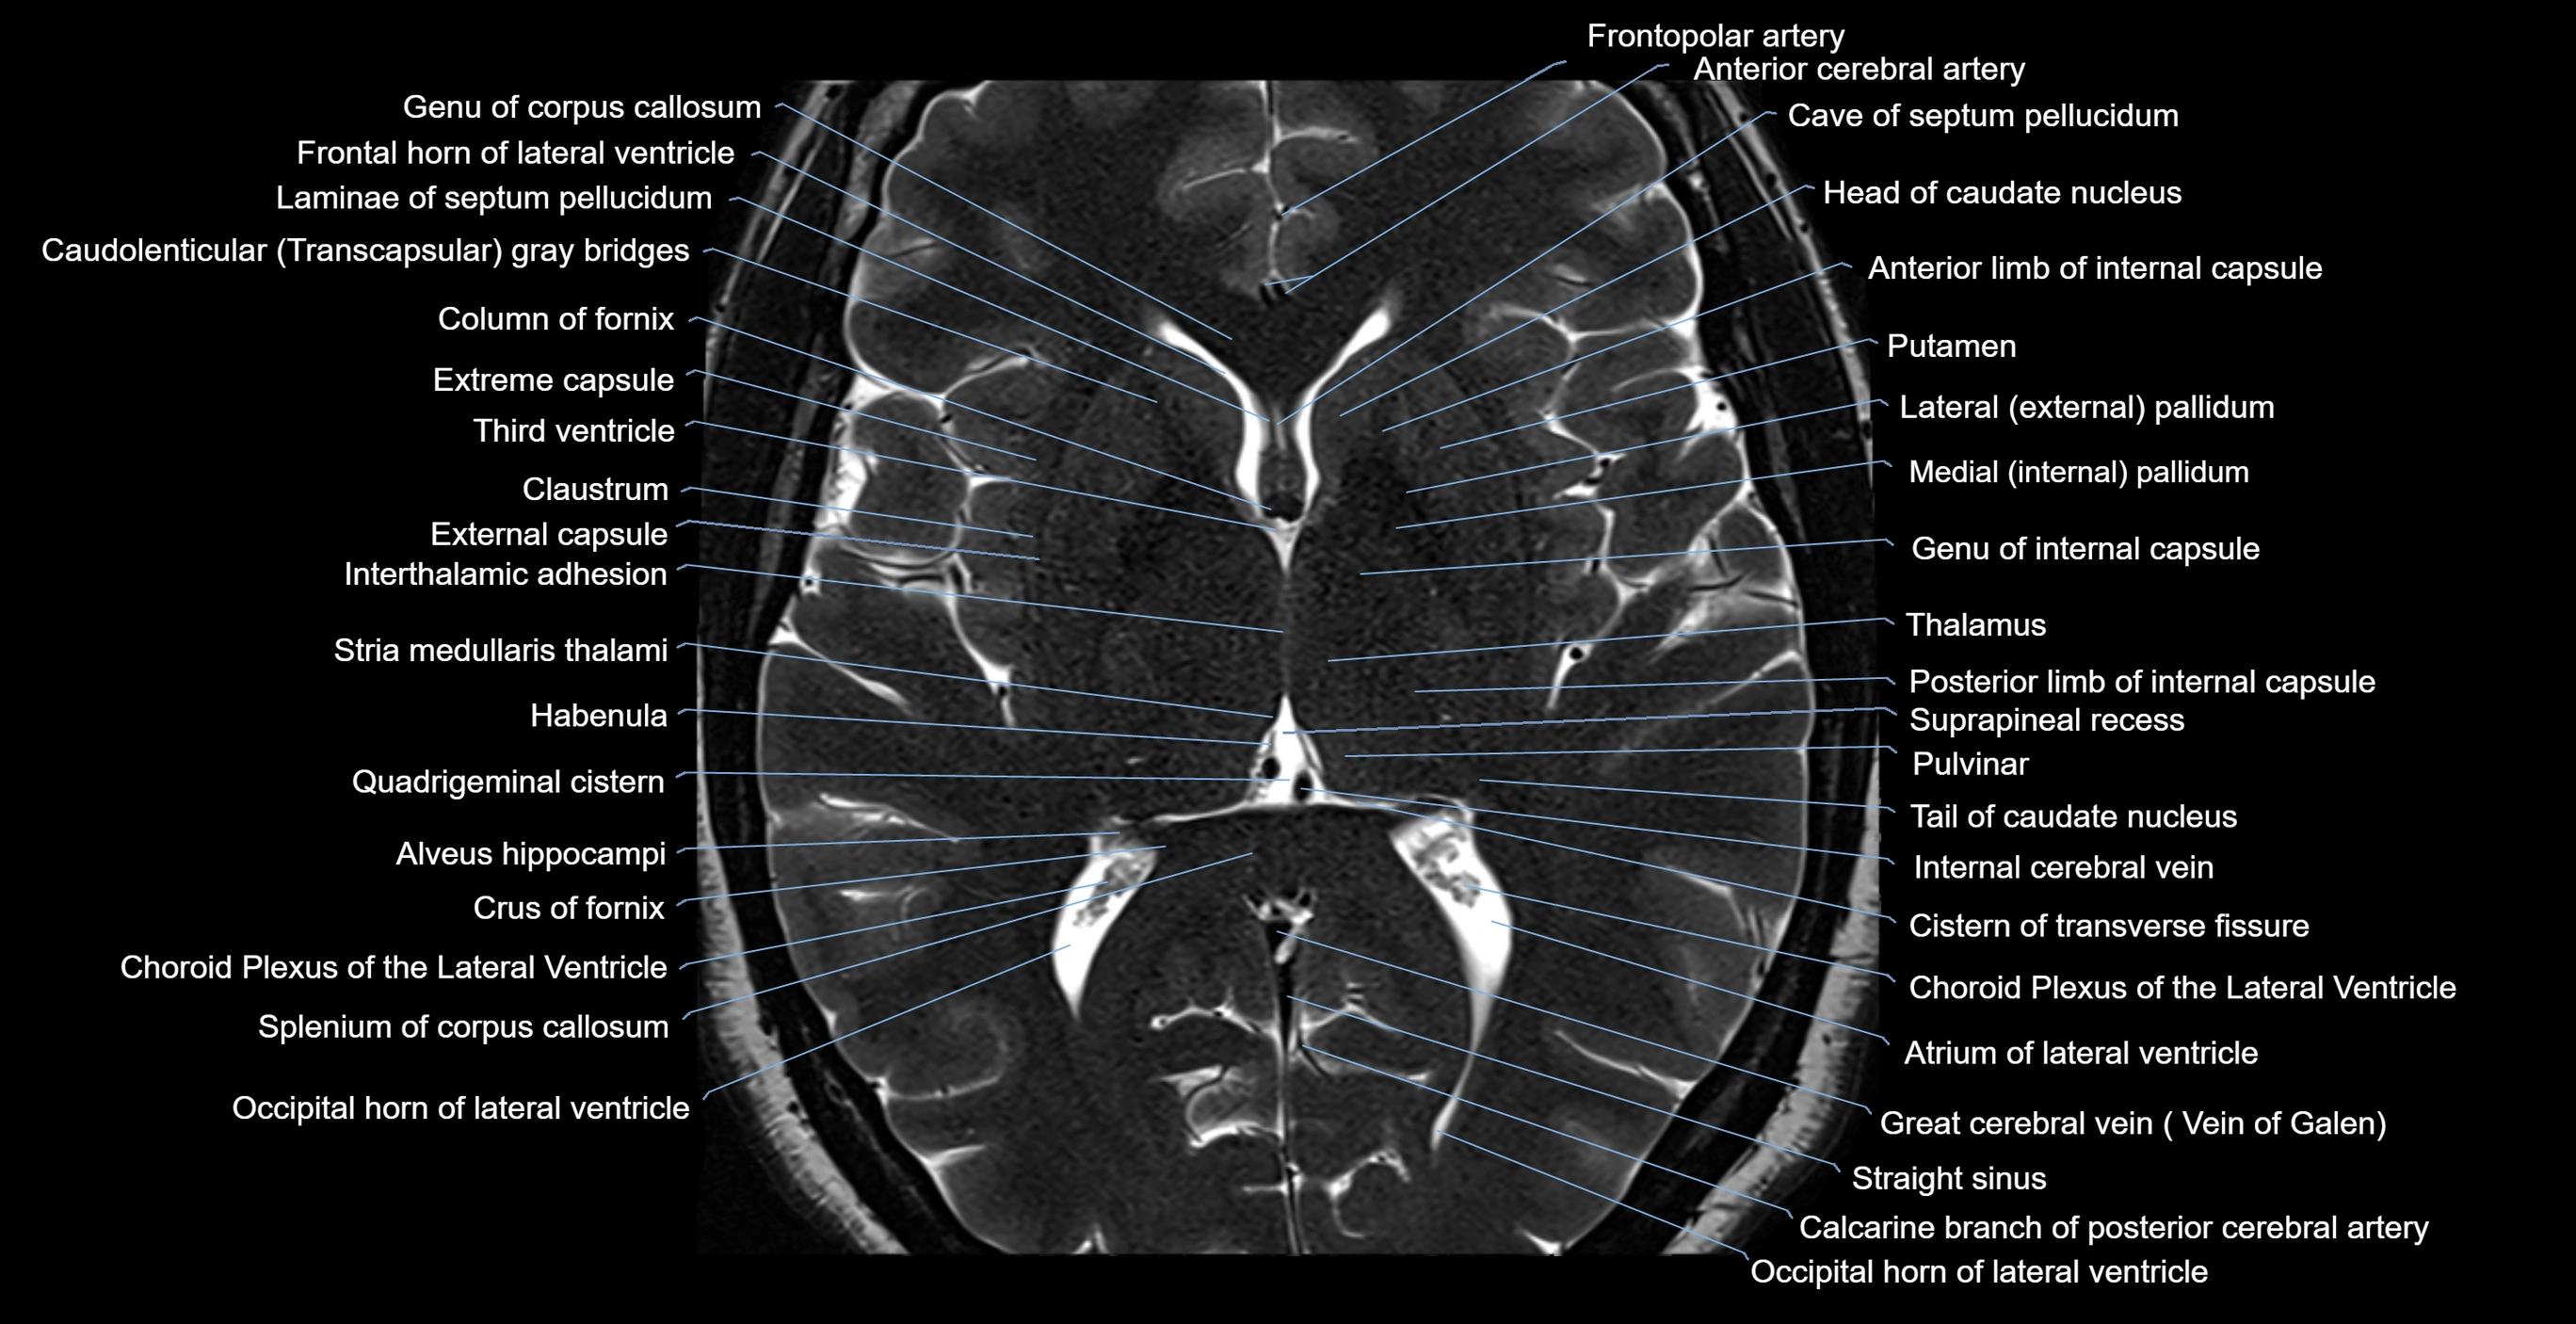

- Atrium of lateral ventricle

- Calcarine branch of posterior cerebral artery

- Cave of septum pellucidum

- Claustrum

- Column of fornix

- Crus of fornix

- External capsule

- Extreme capsule

- Frontal horn of lateral ventricle

- Frontopolar artery

- Genu of corpus callosum

- Habenula

- Head of caudate nucleus

- Interthalamic adhesion

- Lateral pallidum

- Medial pallidum

- Occipital horn of lateral ventricle

- Posterior limb of internal capsule

- Pulvinar

- Putamen

- Quadrigeminal cistern

- Splenium of corpus callosum

- Straight sinus

- Suprapineal recess

- Tail of caudate nucleus

- Third ventricle